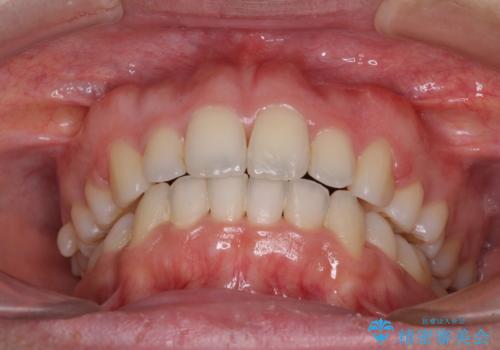

- 前歯のデコボコと口元の突出感を気にして来院された患者様です。

上下左右第一小臼歯4本を抜歯し、ワイヤー装置にて口元を引っ込めるよう矯正治療を行うこととしました。

叢生が強かったため、口元の突出感の改善には限界がありましたが、横側からも口元が引っ込んだ感じが分かるほど改善されました。